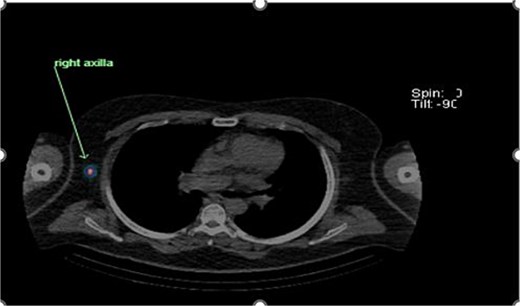

Preoperative lymphoscintigraphy was performed to detect the sentinel lymph node (Fig. 1), expecting it to be in the right inguinal region (Fig. 2). However, drainage to both the right axillary (Fig. 3) and inguinal areas was demonstrated. During surgery, a gamma camera confirmed drainage to both regions (Fig. 4). Blue dye was injected around the previous scar, and sentinel nodes were dissected guided by both blue dye and gamma camera for histopathology.

Intraoperative gamma probe confirming dual drainage to axillary and inguinal regions.

Histology showed no residual malignancy in the re-excision specimen. The right axillary node showed involvement by metastatic melanoma, while the groin lymph node was negative.